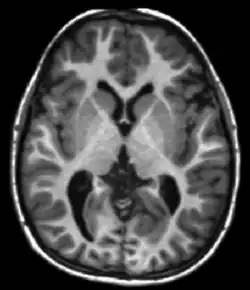

T1 and T2

Each tissue returns to its equilibrium state after excitation by the independent relaxation processes of T1 (spin-lattice; that is, magnetization in the same direction as the static magnetic field) and T2 (spin-spin; transverse to the static magnetic field). To create a T1-weighted image, magnetization is allowed to recover before measuring the MR signal by changing the repetition time (TR). This image weighting is useful for assessing the cerebral cortex, identifying fatty tissue, characterizing focal liver lesions, and in general, obtaining morphological information, as well as for post-contrast imaging. To create a T2-weighted image, magnetization is allowed to decay before measuring the MR signal by changing the echo time (TE). This image weighting is useful for detecting edema and inflammation, revealing white matter lesions, and assessing zonal anatomy in the prostate and uterus.